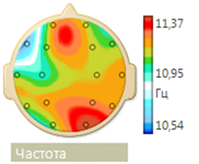

On an EEG, after the first course of stem cell administration, significantly decreased the amount of epileptic formal activity (Figure 5). The frequency of spikes in the left temporal region STI decreased from 30 to 2 per min, the frequency of bilateral synchronization discharges of acute alpha waves remained at the level of 1-2 in minutes. At a frequency of alpha rhythm of 10.5 Hz, normalization occurred of its frequency-spatial structure, but the structure maximum mean coherence values are still was presented in the form of a triangle, which indicated the presence of an active epileptic process.

On the EEG, a disorganized alpha rhythm was maintained with a peak frequency of 12.5 Hz with a diffuse increase in beta activity. Its frequency-spatial structure is largely normalized. A reduction in the pathological structure of the maximum values of mean coherence in the form of a triangle was also noted (Figure 7 & 8).

Figure 7 Frequency-spatial structure of the alpha rhythm with a tendency to normalization (the alpha rhythm of the maximum frequency is located mainly in the occipital region, and the minimum frequency - in the frontal region).